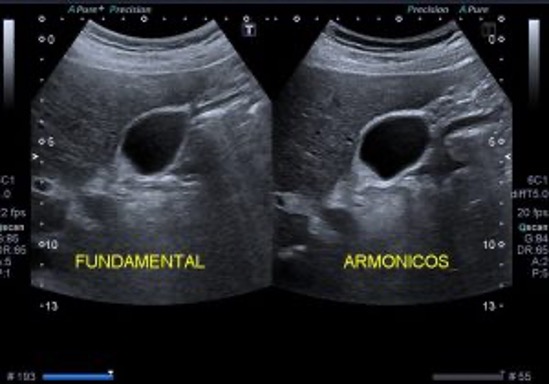

La exploración comienza colocando el transductor en la posición adecuada para visualizar el tendón del subescapular, similar a la técnica utilizada en sedestación. Luego, se realiza un movimiento pasivo del brazo del paciente, quien debe mantenerlo en flexión y abducción de aproximadamente 90 grados. El operador manipula el brazo para encontrar la mejor visualización del labrum anterior, situado en una posición más profunda.